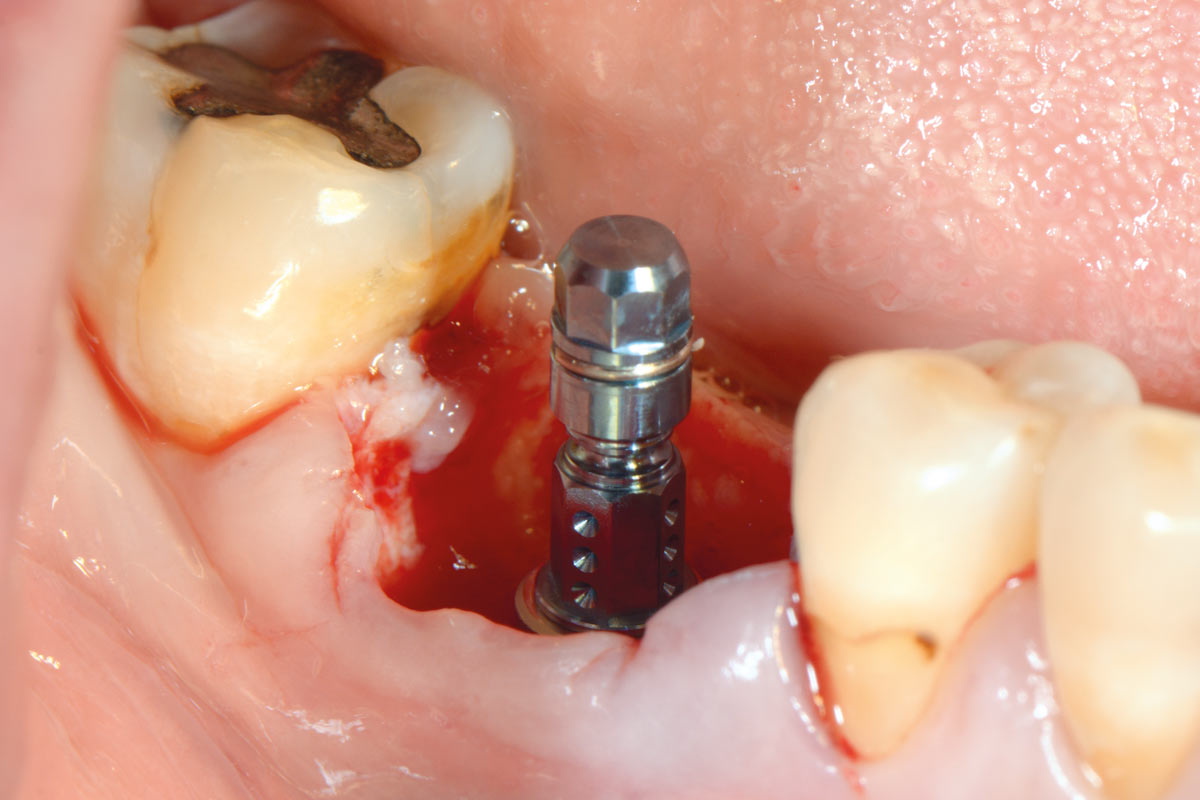

7/19 - Immediate implant placement

Immediate implant placement using maxresorb® - Dr. Alejandro Signorio